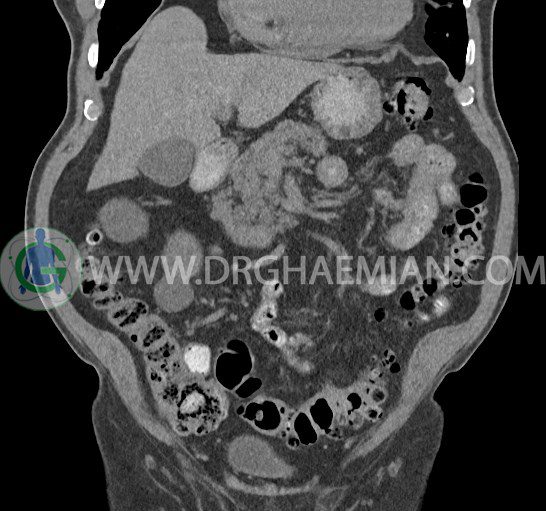

سی تی اسکن لگن یکی از روش های تصویربرداری با سی تی اسکن است. این روش با استفاده از تشعشعات تصاویر عرضی از ناحیه شکمی ایجاد میکند. در این کیس ديورتيكولوزيس، کیست های کورتیکال در هر دو کلیه، لنفادنوپاتی، کلسیفیکاسیون دیواره آئورت و شریان ایلیاک، تغییرات DJD ناحیه توراکولومبار و پروستات بزرگتر از عادی دیده می شود.

در سي تي اسکن اسپيرال شکم و لگن با و بدون کنتراست خوراکی و وريدی (مولتي ديدکتور 16 با مقاطع ظريف و بازسازي هاي ساژيتال و کرونال):

– کيست هاي کورتيکال ساده به قطر 5 mm تا 50 mm در کليه راست و به قطر 5mm تا 55 mm در کليه چپ

– توده ايزودنس به ابعاد mm 17 x 28 در پره ائورت مجاور قسمت تحتاني D3 دئودنوم مطرح کننده لنفادنوپاتي و با احتمال کمتر آنوريسم ترومبوزه (نيازمند مطابقت سونولوژيک)